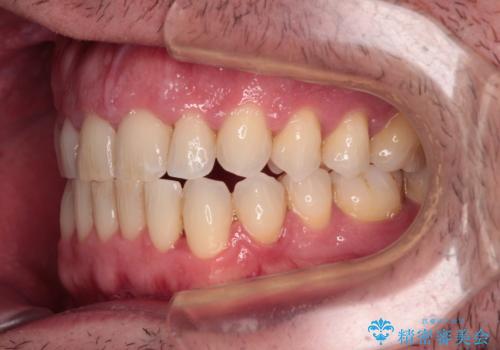

- 前歯でものを噛みきりたいとのことで来院された患者様です。

以前矯正治療を経験されたそうですが、舌の突出癖により上下前歯に隙間ができている様子でした。

前歯の非接触改善は、インビザラインの得意とするところですが、マウスピース矯正は絶対に継続できないとのことで、ワイヤー装置にて矯正治療を行うこととしました。